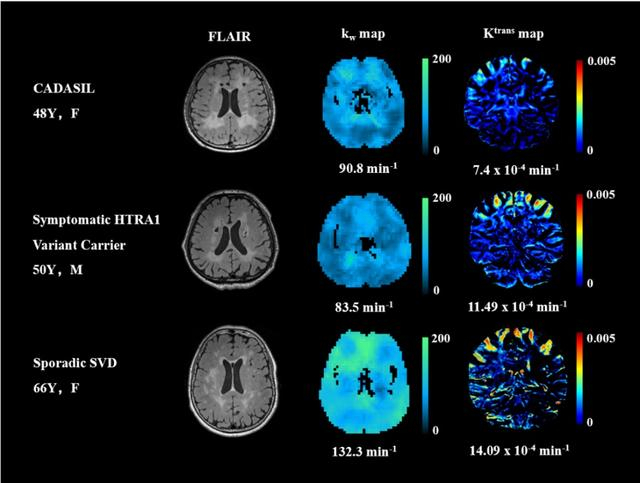

研究纳入40例CADASIL患者、13例HTRA1突变相关脑小血管病患者、30例散发型脑小血管病患者及40例健康对照。研究发现,与健康对照相比,CADASIL组全脑、深部灰质、正常外观白质的血脑屏障水交换率均降低,而血脑屏障渗漏率无显著差异;HTRA1相关组全脑、深部灰质、正常外观白质的血脑屏障水交换率降低,且全脑的血脑屏障渗漏率升高;散发型组全脑和正常外观白质的血脑屏障渗漏率升高,而血脑屏障水交换率无显著差异(图1、2)。

图1 三组cSVD的kw及Ktrans图示例